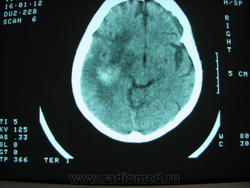

Смущают мелкие гиподенсивные зоны кпереди от гиперденсивного участка на первом снимке. Клинику бы по подробней "в анамнезе травма" как то слишком мало. Вообще первое мнение было лизирующаяся гематома с перифокальным отеком. Опухоль с кровоизлиянием таких размеров, ИХМО, дала бы больший пальцевидный отек и дислокацию.

В дифряд включила бы метастазы меланомы. Большеват отек и масс-эффект для трехнедельной гематомы. Контроль через 2-3 недели.

У больной цироз и асцит.Дообследование с контрастом затруднительно.Предыдущие сканы снять пока не смог.